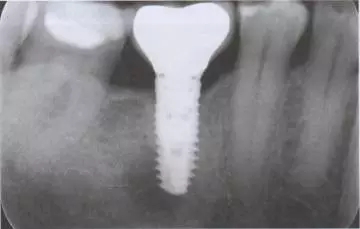

在口腔外科治療中, 拔牙后疼痛是最常見的并發(fā)癥,其成因有很多種因素5。通過拔牙造成牙糟骨創(chuàng)傷的因素, 除了患者特定因素外, 其它的還有如一般健康狀況、藥物、尼古丁和酒精5,15。由于感染調(diào)節(jié),使細菌滲透到牙糟骨內(nèi)并形成骨炎,其中患者會因由此所造成的神經(jīng)炎而產(chǎn)生強烈的癥狀。在序列拔牙中, 術(shù)后疼痛的出現(xiàn)與單顆牙拔除相比卻鮮有被報道15。然而在即刻種植后, 這可能會因患者要求拔出種植體而導致產(chǎn)生劇烈的疼痛; 或者在另一方面會顯示, 造成種植體底端出現(xiàn)種植體周圍炎癥狀。如果出現(xiàn)這樣的情況,是非常難以治療的,因為感染的病灶通常位于舌側(cè),而通過外科手段進入骨溶解區(qū)兒乎是不可能的(圖1至7)。

圖1 圖2

圖1 患者46牙根管再治療失敗,出現(xiàn)根尖炎癥,準備拔除做即刻種植

圖2 小視野CBCT圖像顯示種植修復(fù)一年后的骨容解情況